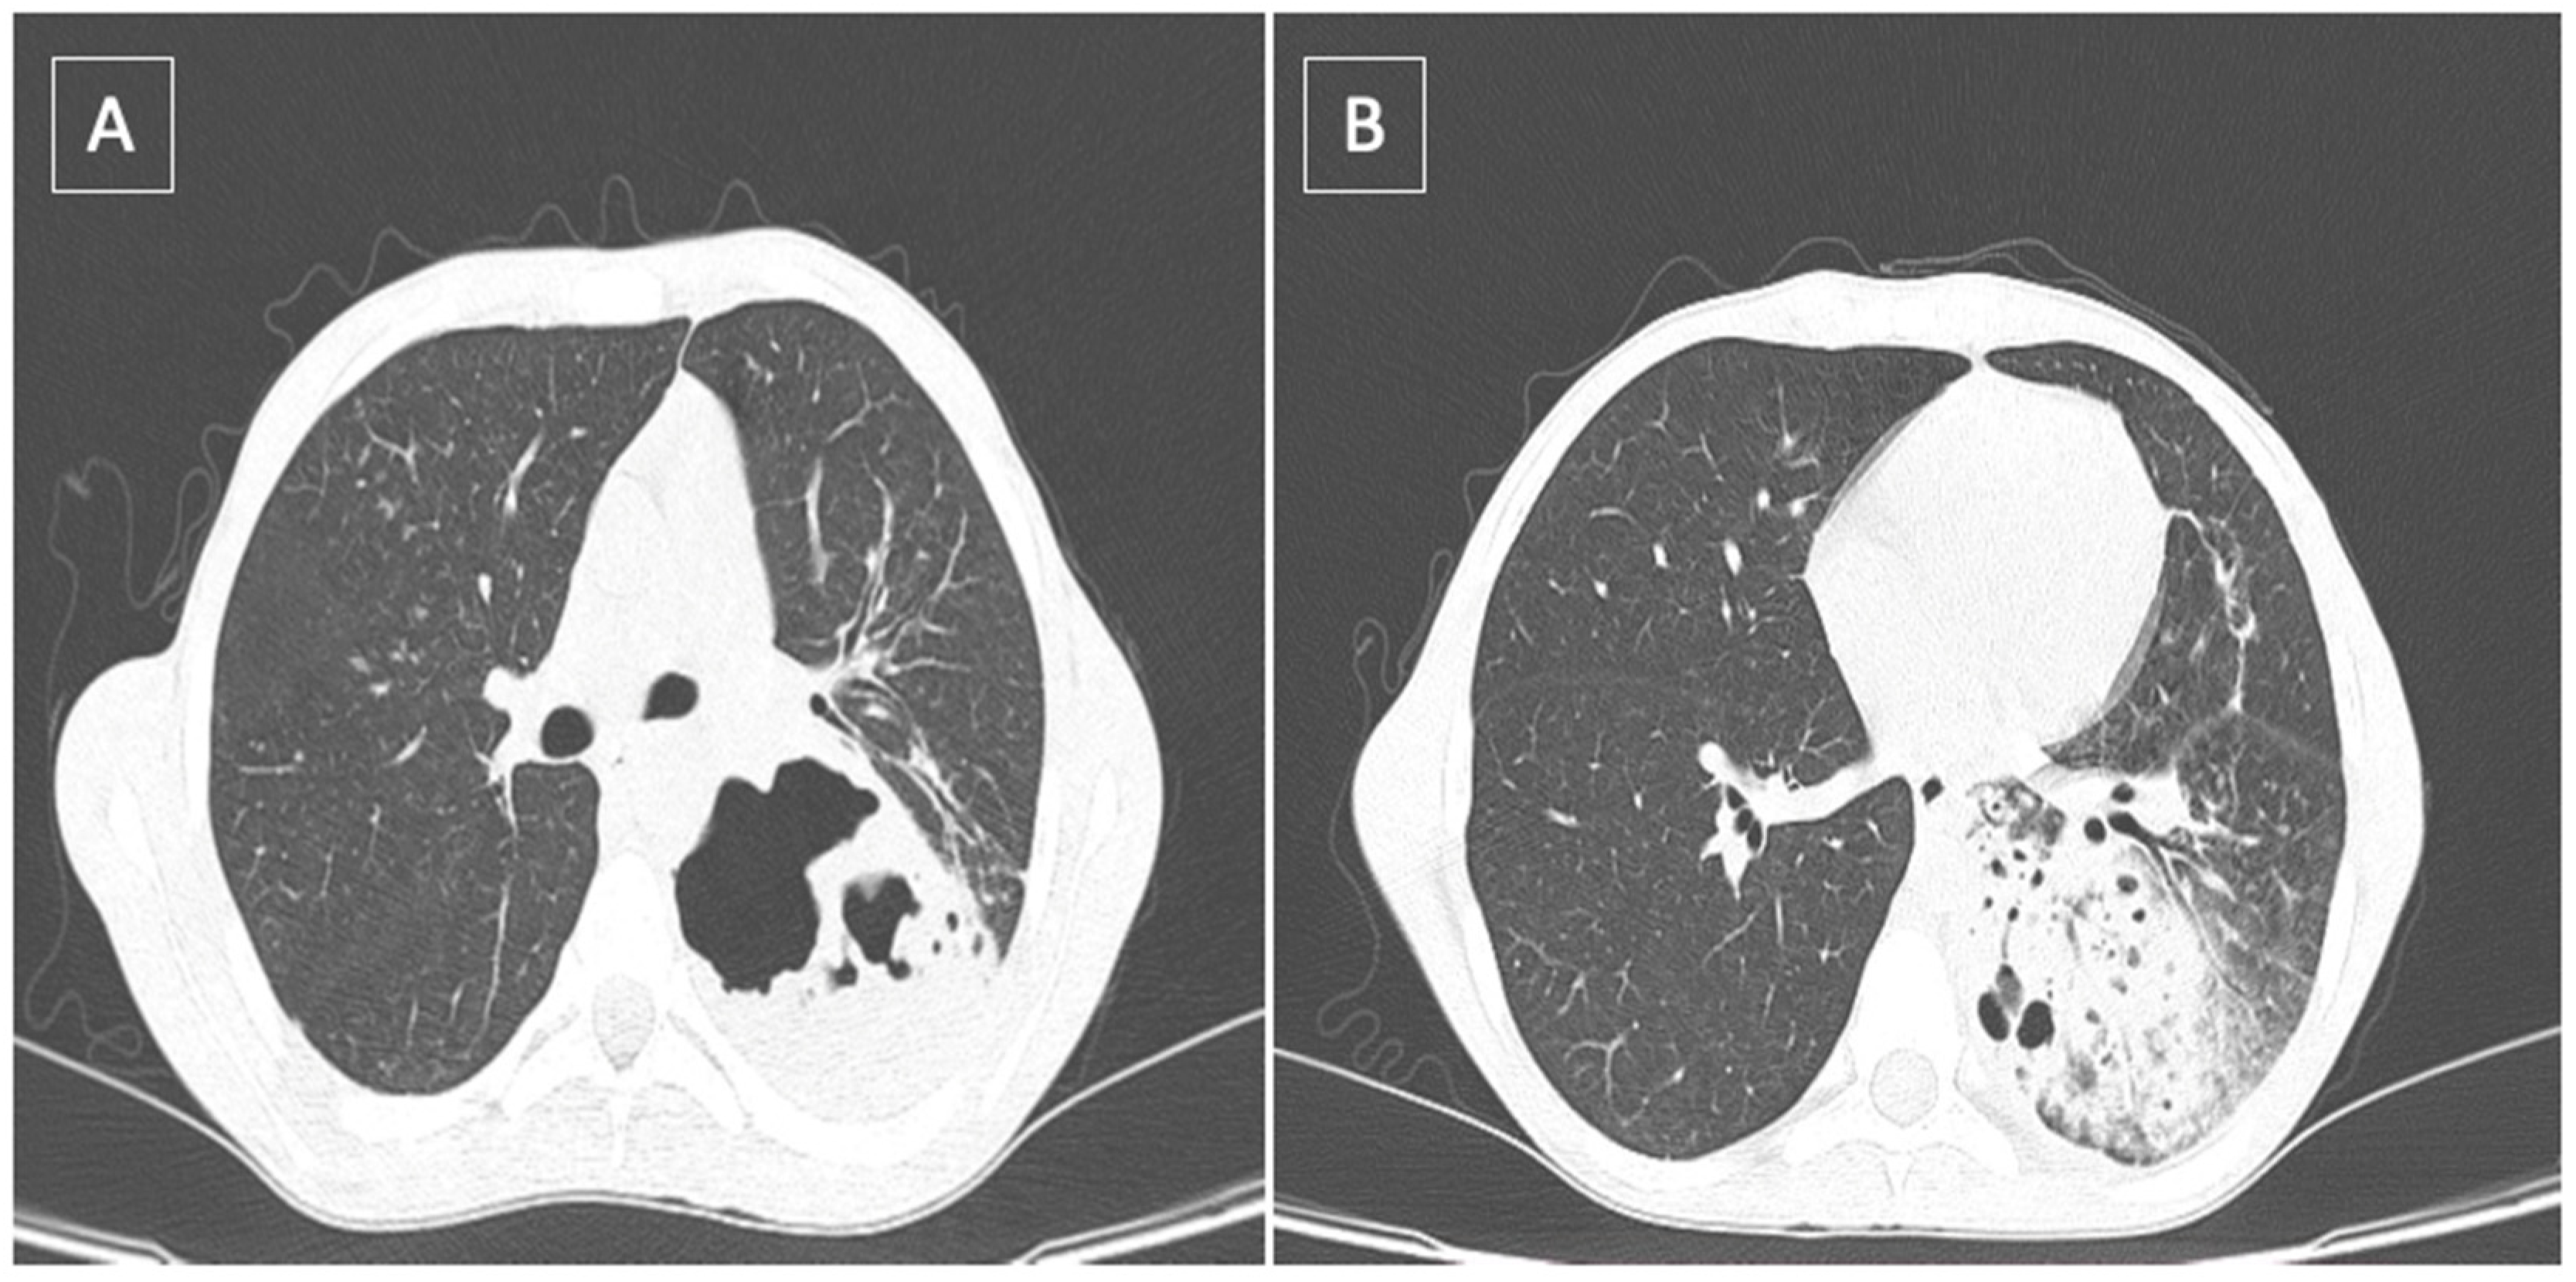

- Large airway involvement with stenosis, bronchitis, bronchiectasis and pulmonary suppuration;

- Parenchymal involvement with lymphocytic alveolitis, parenchymal infiltrates and granulomatous bronchioles;